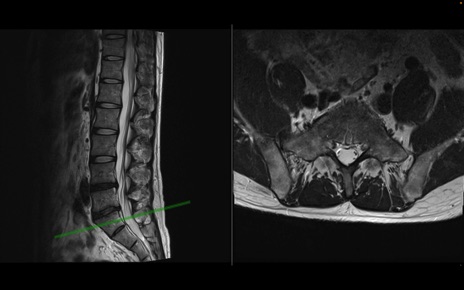

【症例】40歳代男性

【主訴】左臀部〜大腿後面痛み

【現病歴】2週間前から腰痛あり。2日前に夜中にくしゃみをした際に激痛が出現。疼痛強いため来院。

【身体所見】左臀部〜大腿後面、下腿後面のしびれ。SLR -/+ 30度、うつ伏せ困難、筋力低下なし。

異常所見と診断は?